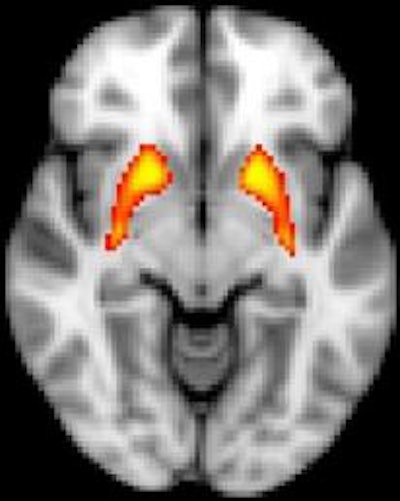

fMRI shows dysfunction in the striatum, which is associated with psychosis risk. Image credit: John Kerns.

Using a feedback-based learning task, lead author Nicole Karcher and colleagues found that people at risk for psychosis are impaired when they need to rely on feedback to learn. More specifically, fMRI brain scans revealed that the striatum failed to activate in people at risk for psychosis when they received feedback, according to study results published online March 24 in Schizophrenia Bulletin.